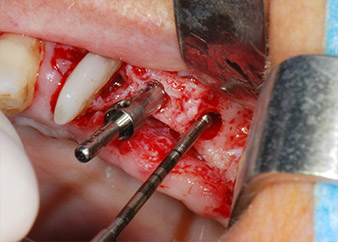

Abb. 8: Der nächste Schritt ist die rotierende Präparation des Implantatbetts bis kurz unterhalb des Sinusbodens an Position 25, die mit einem weiterentwickelten Implantatmotor erfolgte.

Im folgenden Schritt wurde das jeweilige Implantatbett an den Positionen 25 und 26 mit rotierenden Instrumenten in einem Winkelstück mit einem Übersetzungsverhältnis von 20:1 (WS-75 L G, W&H) und einem vor Kurzem aktualisierten leistungsstarken Implantatmotor präpariert (Implantmed, W&H) (Abb. 8 und 19).

Dann wurden die Implantate (Restore, Keystone Dental) mit dem Implantatmotor eingesetzt (Abb. 11 und 12).

Insertion des Implantats an Position 26

Abb. 11: Insertion des Implantats an Position 26 bei geringer Geschwindigkeit und einer Drehmomentbegrenzung von 35 Ncm.

Eindrehen der Abdeckschrauben

Abb. 12: Beide Implantate sind in Position und bereit für das Eindrehen der Abdeckschrauben.